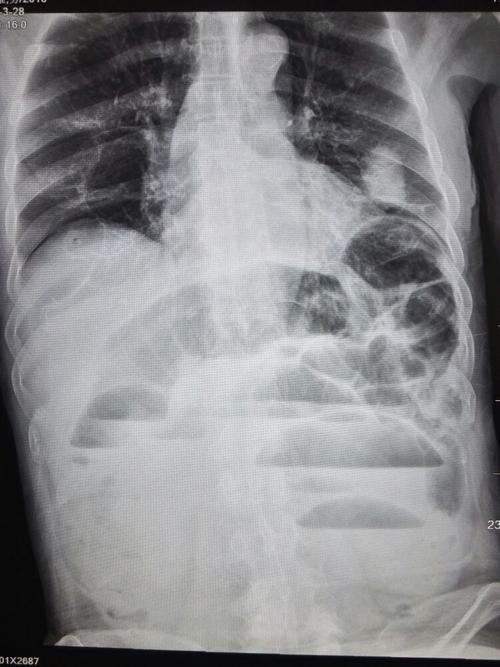

入院后立位腹平片如图所示:多发气液平面,提示肠梗阻!